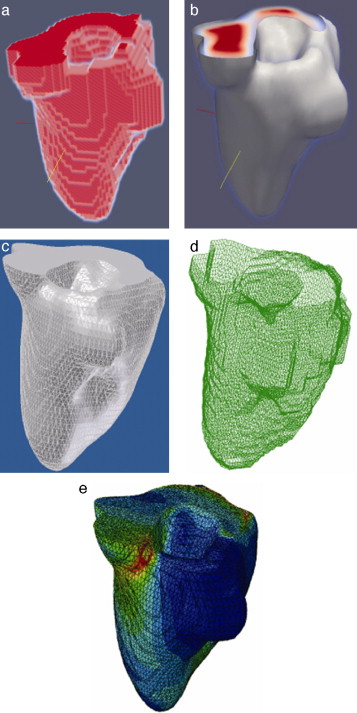

En el siguiente paso, se realizó el remuestreo del modelo geométrico segmentado empleando dilatación morfológica con un elemento estructural en forma de esfera de radio 3 × 3 × 3 . Esta tarea fue necesaria para suavizar superficies superpuestas y rellenar posibles agujeros generados durante la segmentación. Este modelo fue guardado en formatos legibles por software de visualización y herramientas CAD como GiD, ParaView, Autodesk Inventor y Abaqus.

3.1.4. Pruebas de discretización

Finalmente, empleando estas herramientas, se aplicaron condiciones de contorno de prueba en zonas aleatorias del modelo, verificándose la utilidad del modelo geométrico para su discretización con el método de elementos finitos.

En la figura 16 se presenta el volumen final del ventrículo izquierdo con el inicio de la válvula aórtica (fig. 16 .a), el modelo final suavizado visualizado en ParaView (fig. 16 .b), el modelo en sólido visualizado en Autodesk Inventor (fig. 16 .c), el modelo en malla visualizado en GiD (fig. 16 .d) y el modelo discreto con los elementos finitos realizado con Abaqus (fig. 16 .e). Estos modelos han sido obtenidos a partir de IRM cardiovascular de un paciente con cardiopatía isquémica. Obsérvese que la protuberancia presente en la zona superior derecha del ventrículo izquierdo constituye una zona de necrosis conocida como cicatriz isquémica, la cual es alojada en el músculo del miocardio.

|

Figura 16. Vista tridimensional de ventrículo izquierdo. (a) Volumen original visualizado con ParaView. (b) Volumen original suavizado con morfología matemática visualizado con ParaView. (c) Sólido del volumen generado con Autodesk Inventor. (d) Mallado del volumen generado con GiD. (e) Modelo discreto con el método de elementos finitos generado con Abaqus empleando condiciones de contorno de prueba. |